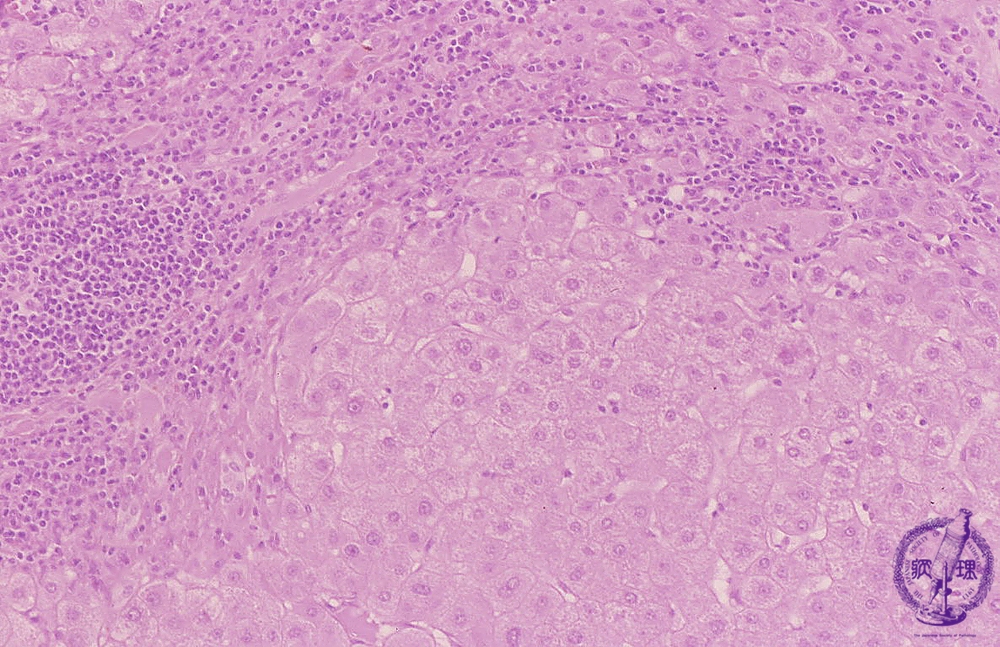

Microscopic image (HE stain, intermediate power): Liver cirrhosis due to chronic hepatitis. Lymphocytes infiltrate fibrous septa (blue arrow) and at the periphery of regenerative nodules there is interface hepatitis with hepatocyte drop-out (red line). Changes attributable to persistent chronic hepatitis C viral infection are simultaneously observed.